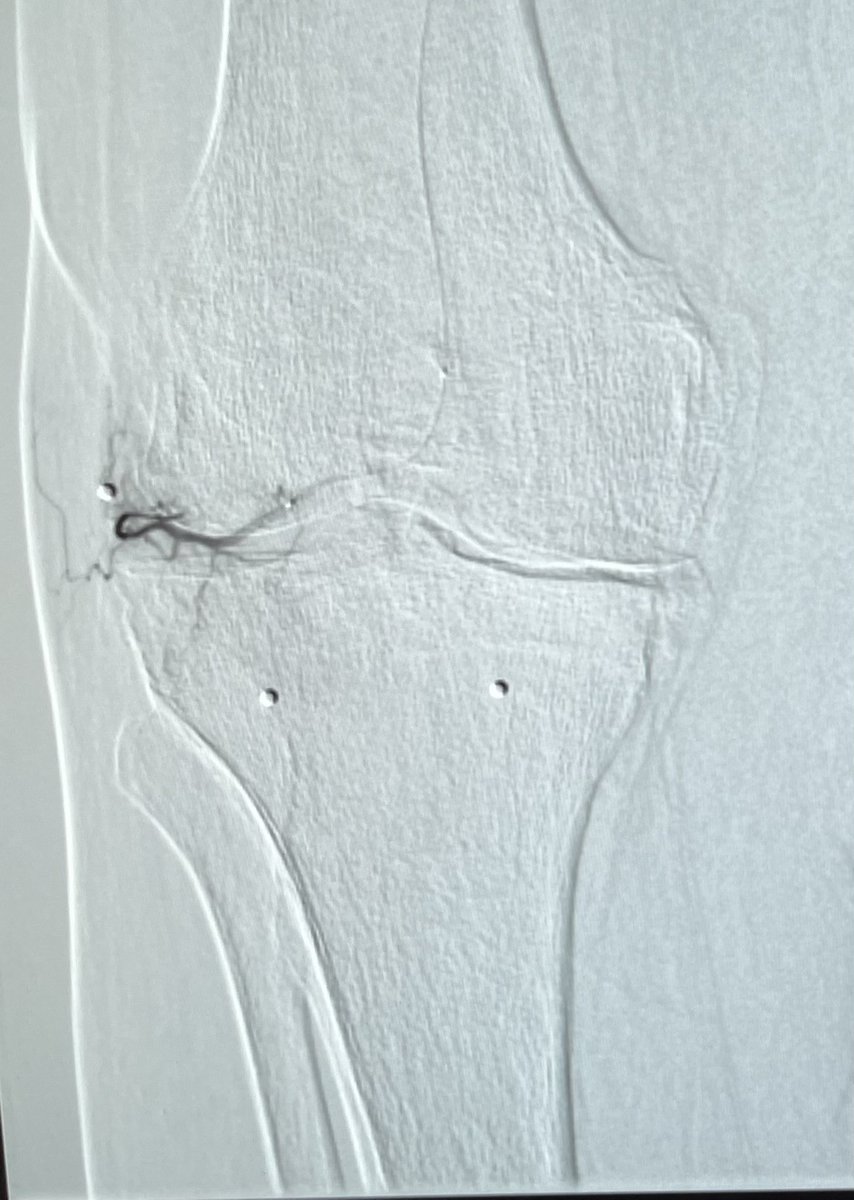

Genicular Artery Embolization Technique - ⁦@IrColorado⁩ ⁦@SterbisEmily

Genicular Artery Embolization for knee osteoarthritis. No skin mottling or ulcers. @IrColorado